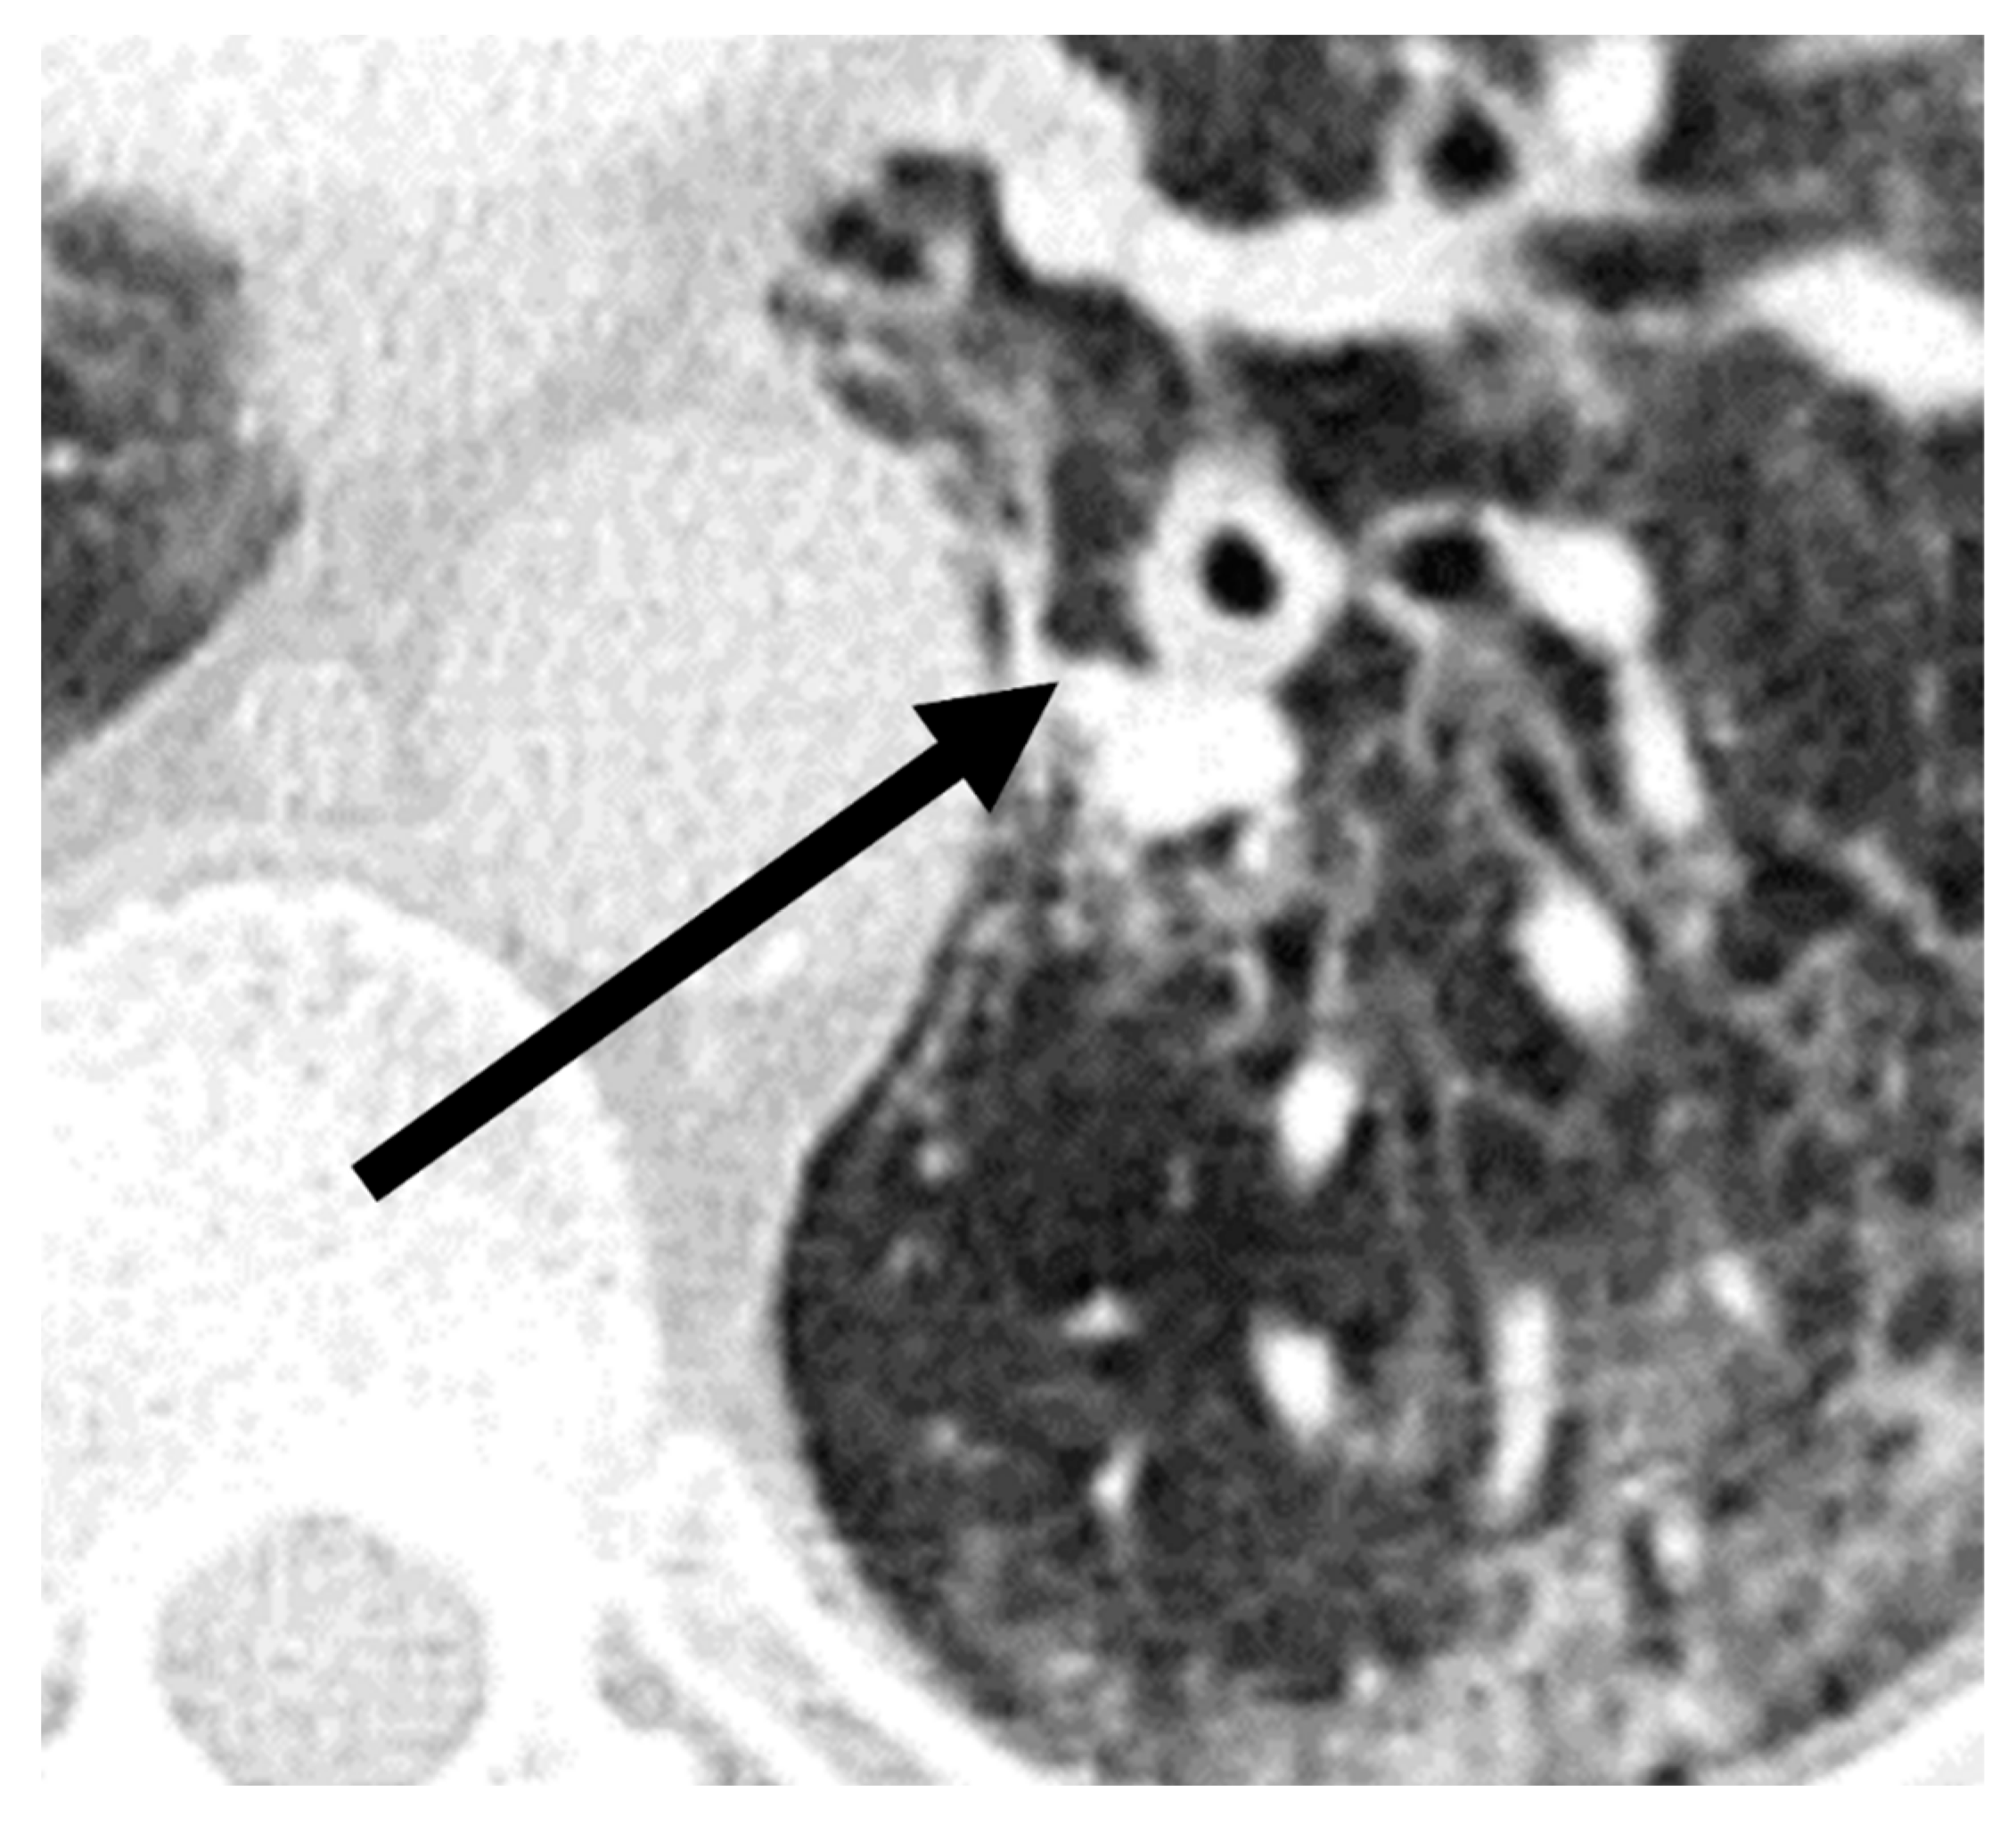

| Bronchial wall thickening | 26.9% (14/52) | 61.5% (8/13) | 0.03 | 0.89 |